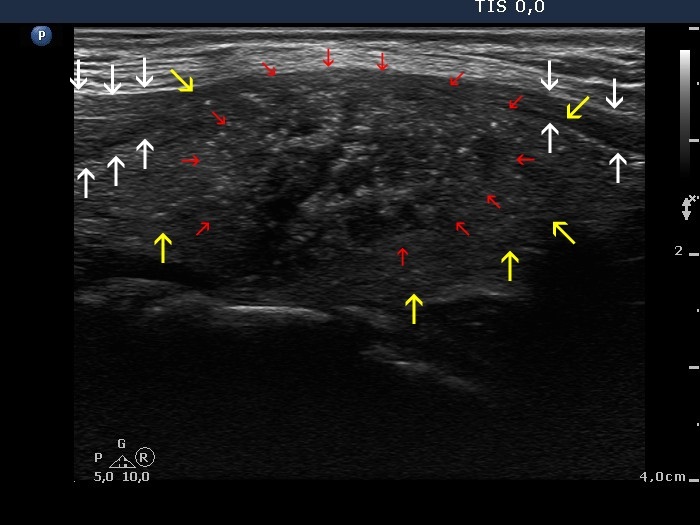

Lymph nodes - case conp 005 (ultrasonographic picture 4b)

Left lobe, longitudinal scan. The contour of the lobe is marked with yellow arrows, the contour of the tumor is marked with red arrows. As a consequence of bulging of the tumor, the sternocleidomastoid muscle became narrow. The normal part of the muscle is marked with white arrows.